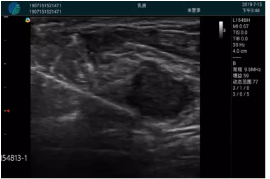

清晰顯示腺體內(nèi)低回聲快影,邊界清晰,包膜較光滑

確定進(jìn)針路徑并實(shí)時(shí)監(jiān)測(cè)抽吸針與腫塊位置關(guān)系

抽吸針進(jìn)入腫塊內(nèi)部進(jìn)行旋切

抽吸過程中可見腫塊明顯縮小,并根據(jù)腫塊位置改變針道位置

抽吸旋切后再進(jìn)行超聲復(fù)查,原腫塊區(qū)域未見殘留組織及出血